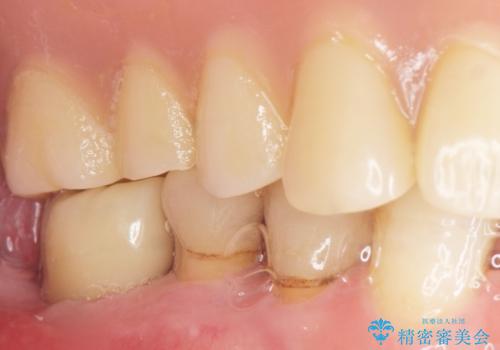

奥歯のインプラント 70代男性

- 奥歯の違和感を主訴に来院された患者様です。

精査したところ、右下の奥歯は大きなう蝕により保存不可能な状態でした。

患者様のご希望により、抜歯後インプラント治療を行いました。